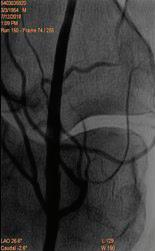

60 КЪСНА РЕВАСКУЛАРИЗАЦИЯ СЛЕД ОСТРА ТРОМБОЗА НА А. СУБКЛАВИА СИНИСТРА –КЛИНИЧЕН СЛУЧАЙ Р. Рунков

62 РЕТРОГРАДНА ПЕРКУТАННА